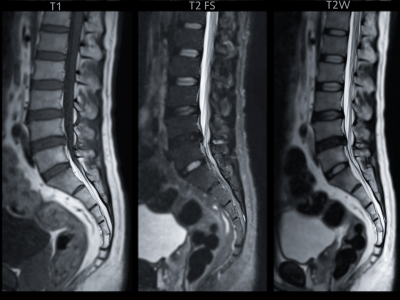

Röntgen, MR & Ultraljud

Kan vara en del av vägen till din diagnos.

Vi börjar alltid med en grundlig klinisk funktionsanalys. Bilddiagnostik används som ett precisionsverktyg när vi behöver bekräfta fynd eller utesluta bakomliggande orsaker som inte syns vid en manuell undersökning.

Misstanke om diskbråck: För att se exakt om och hur en nerv ligger i kläm i nacken eller ländryggen använder vi MR (Magnetkamera).